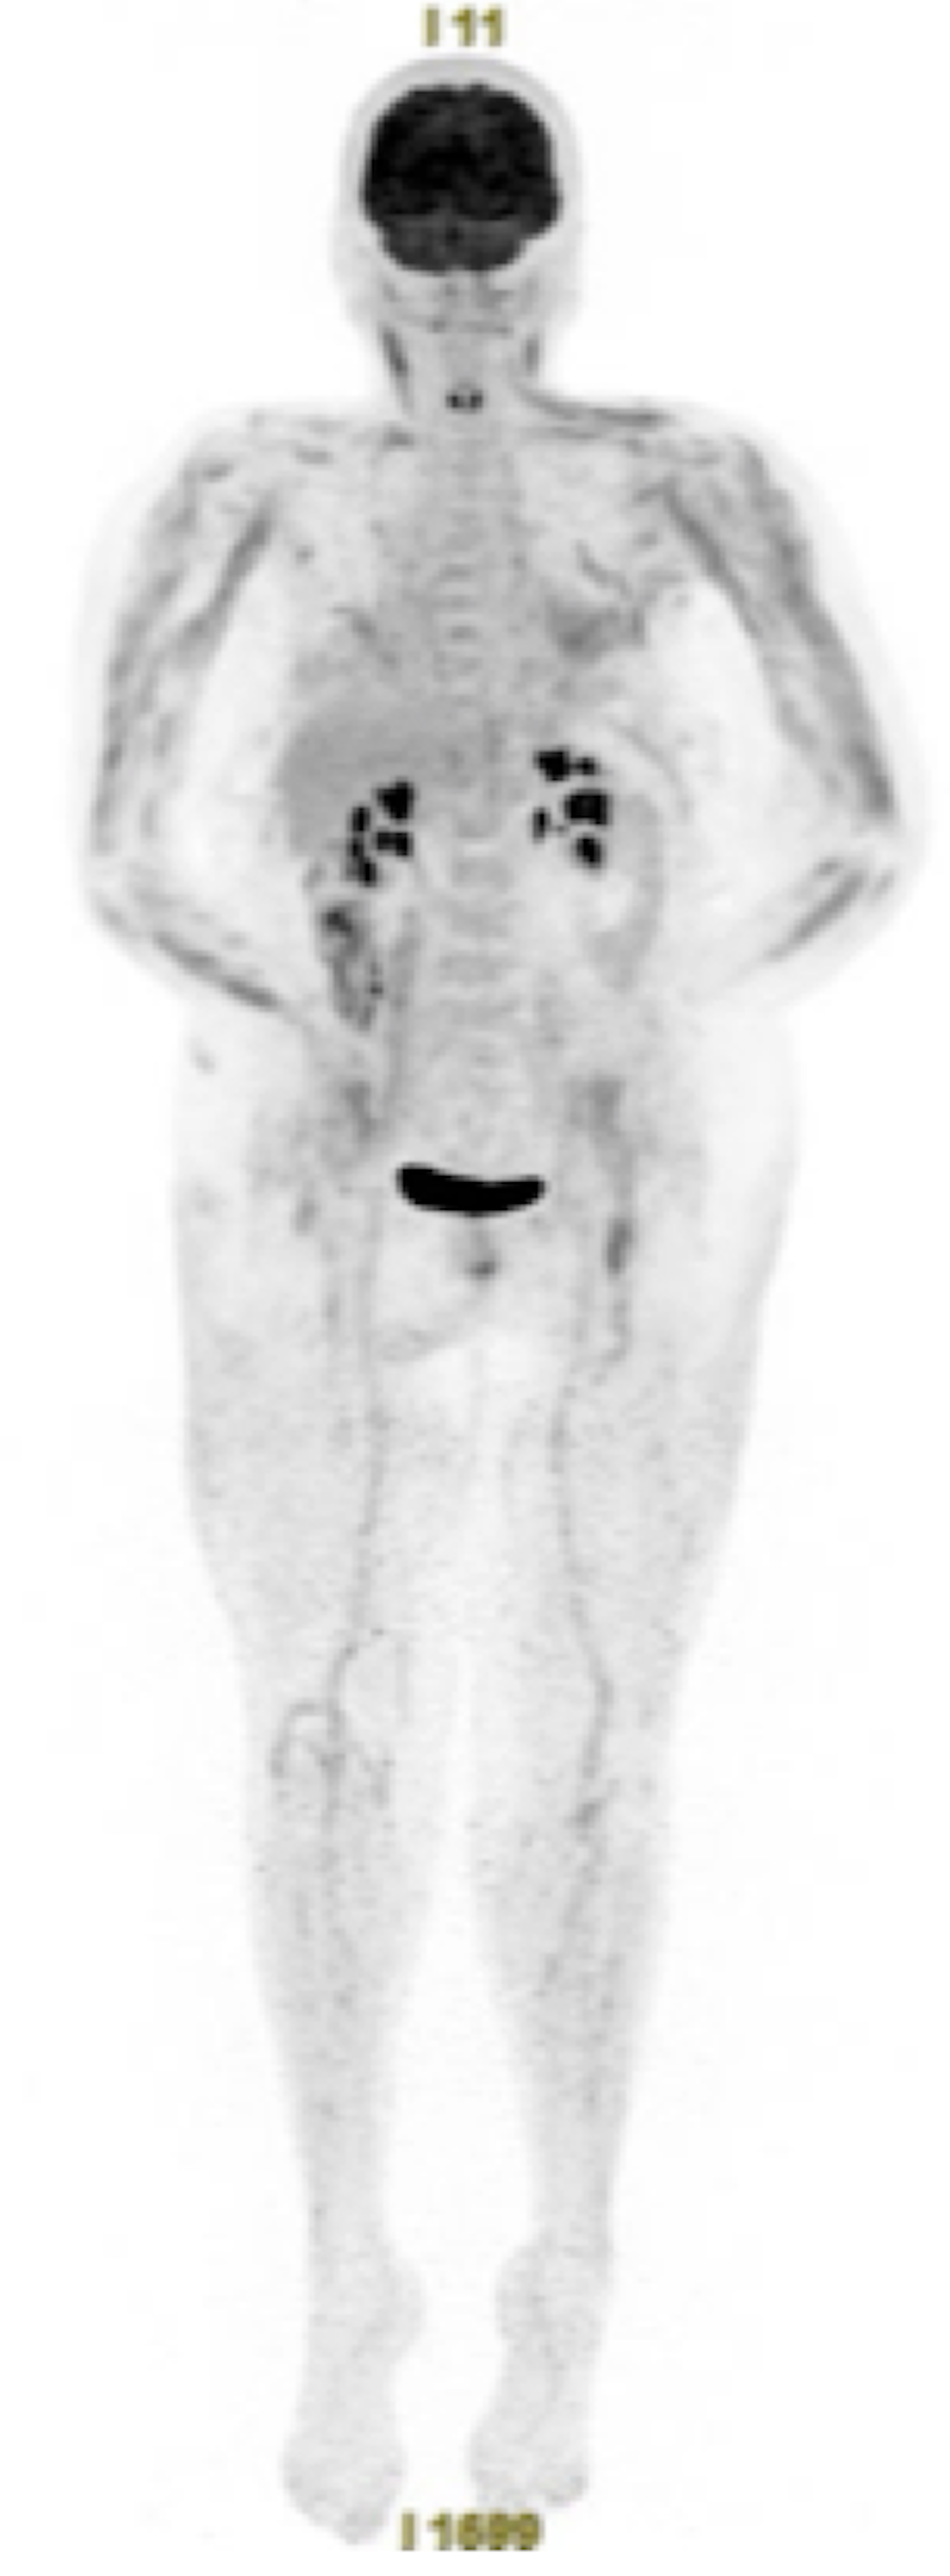

Oui Thibault c’est bien une Dermatomyosite prédominant aux membres supérieurs et le signe clinique est bon !

Par contre ce n’est pas un nodule de carcinose ni l’appendice…

Ok! Alors pourquoi pas une atteinte inflammatoire colique (colite ulcéreuse?) devant un hypermétabolisme segmentaire du colon droit, épaississement pariétal, infiltration de la graisse adjacente et ganglion inflammatoire dans le territoire de drainage.

Oui c’était une néoplasie plan du caecum non vue à la TEP avec adénopathie satellite.

Et c’était un tableau de Dermatomyosite paranéoplasique avec pneumopathie interstielle diffuse non spécifique qui se caractérise par son gradient apico-basal entre autre.